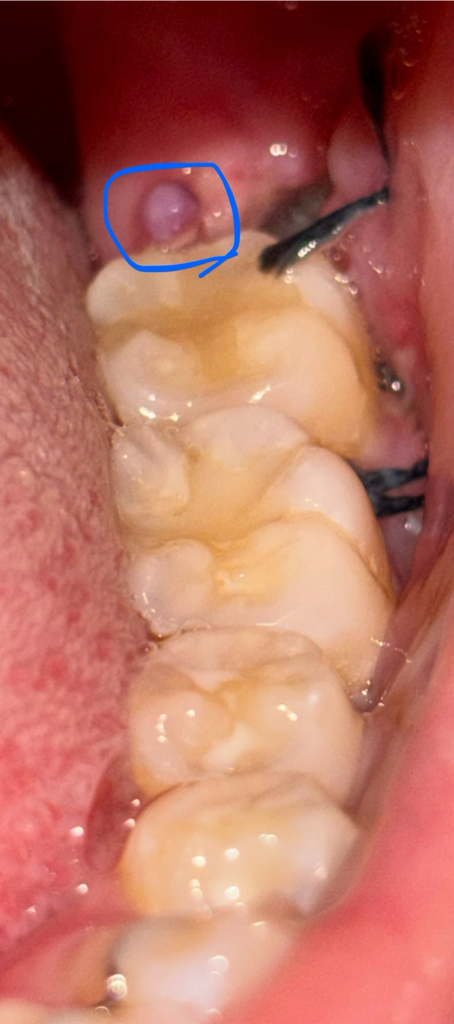

사랑니 매복 발치 후 염증인가요? (사진첨부)

사랑니 매복이어서 발치한지 4일이 지났는데

그 자리에 뾰루지같이 볼록한게 생겼어요

너무 따갑고 떨어질거같은데 혹시 염증인가요?

심각한건가요?ㅠㅠ

• 1번 째 사진

잇몸을 절개하고 발치를 하고나서 자연스럽게 생기는 현상입니다. 너무 걱정하지 않으셔도 됩니다.

혈병이 형성된 것으로 보이며, 억지로 제거하지 않아도 되며, 자연스럽게 아물면서 탈락되게 됩니다. 해당부위에 염증이 덧나지 않도록 헥사메딘 가글액으로 소독을 하길 권합니다.

염증상태로 보여집니다 치과에서 처방된 항생제, 진통제를 추가로 복용하는 것과 온수세정등이 필요해보이며 치과 내원하여 진료를 보시기 바랍니다. 아주 심각하거나 그렇지는 않습니다